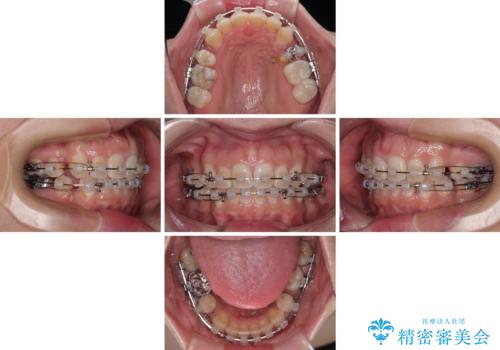

- 矯正装置

- クリアブラケット

- 口元の突出感と奥歯のむし歯を気にして来院された患者様です。

奥歯の虫歯は事前に矯正治療用の仮歯に置き換えて矯正治療を行い、装置除去後にセラミッククラウンにて補綴治療を行うこととしました。

通常は上下左右の第一小臼歯4本を抜歯することになりますが、左側下顎の第二小臼歯は既に根管治療をされており、予後が良くないとのことでこの歯を抜歯し、ワイヤー装置にて矯正治療を行うこととしました。